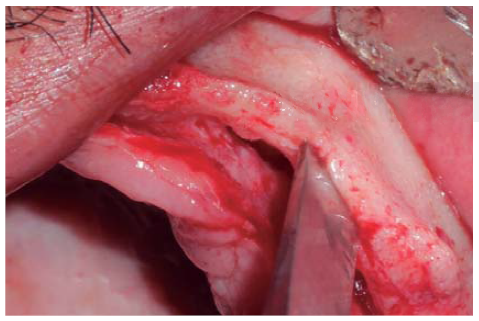

A full thickness incision over the crest was performed, raising a mucoperiosteal flap exposing bone table up to 4 mm from the top of the crest in vestibular direction; from that point the flap was divided into partial thickness (Figure 3). After this, impact points were marked in designated places according to surgical guide for implant placement; perforations were initiated with a 1.6 mm diameter burr in order to determine desired implant depth and axis. After this, a ridge was created on the crest with a diamond burr, fracturing cortical bone to create chisel's access to cancellous bone, and with the aforementioned, bone tables were separated until reaching a 5 mm depth (Figures 4 y 5). Perforations were further continued with a 2.0 diameter burr (Figure 6), and vestibular table expansion was undertaken creating greenstick fracture with the expanders, until reaching sufficient osseous bed diameter (3.2 mm diameter) (Figures 7 y 8). Implants were then placed at a 25 rpm speed and 35 Nem torque (Figures 9 y 10). After this, a particulate bovine bone graft was placed (Bonefill® Bionnovation Biomedical, Sao Paulo, Brazil) with the aim of preserving integrity of vestibular bone tables (Figure 11). All these procedures were repeated for placement of all six implants. Finally, sutures were undertaken with monofilament nylon 5/0.

Figure 5 Bone chisel entering medullar portion, separating cortical ridge leading to greenstick fracture.